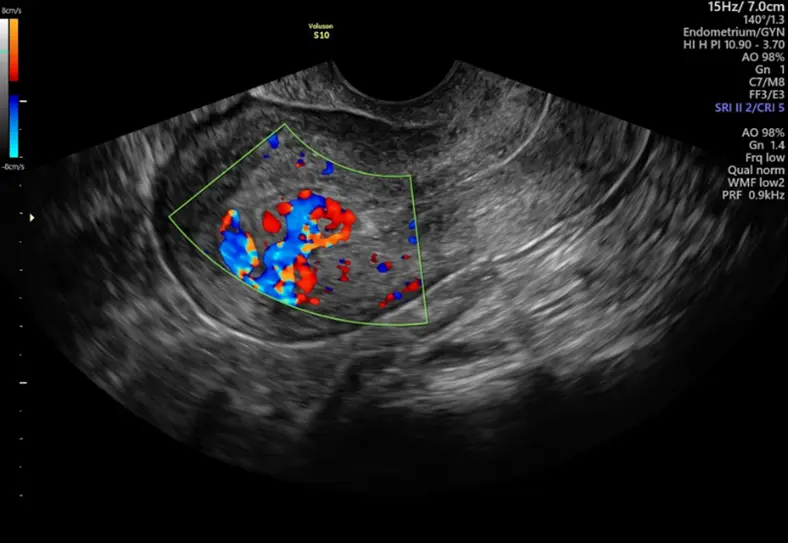

RPOC: Understanding Persistent Bleeding After Delivery or Miscarriage

RPOC (Retained Products of Conception) occurs when placental or fetal tissue remains in the uterus after delivery, miscarriage, or abortion. It can cause persistent bleeding, infection, and long-term complications if not detected early.